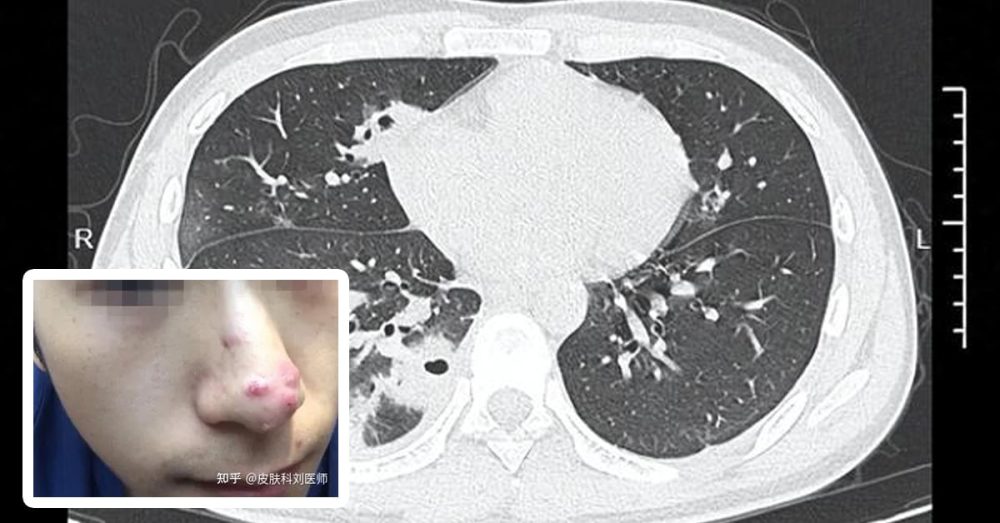

几天后,痘痘不仅没有好转,小林更出现发烧、剧烈咳嗽、咳痰及右下胸部刺痛等症状。医院详细检查后发现,他的肺部布满十多个大小不一的空洞,部分位置已有坏死现象,诊断为“血源性肺脓肿”。

医生指出,痘痘被不洁操作挤破后,细菌可能进入血液,再扩散至肺部,引发严重感染。